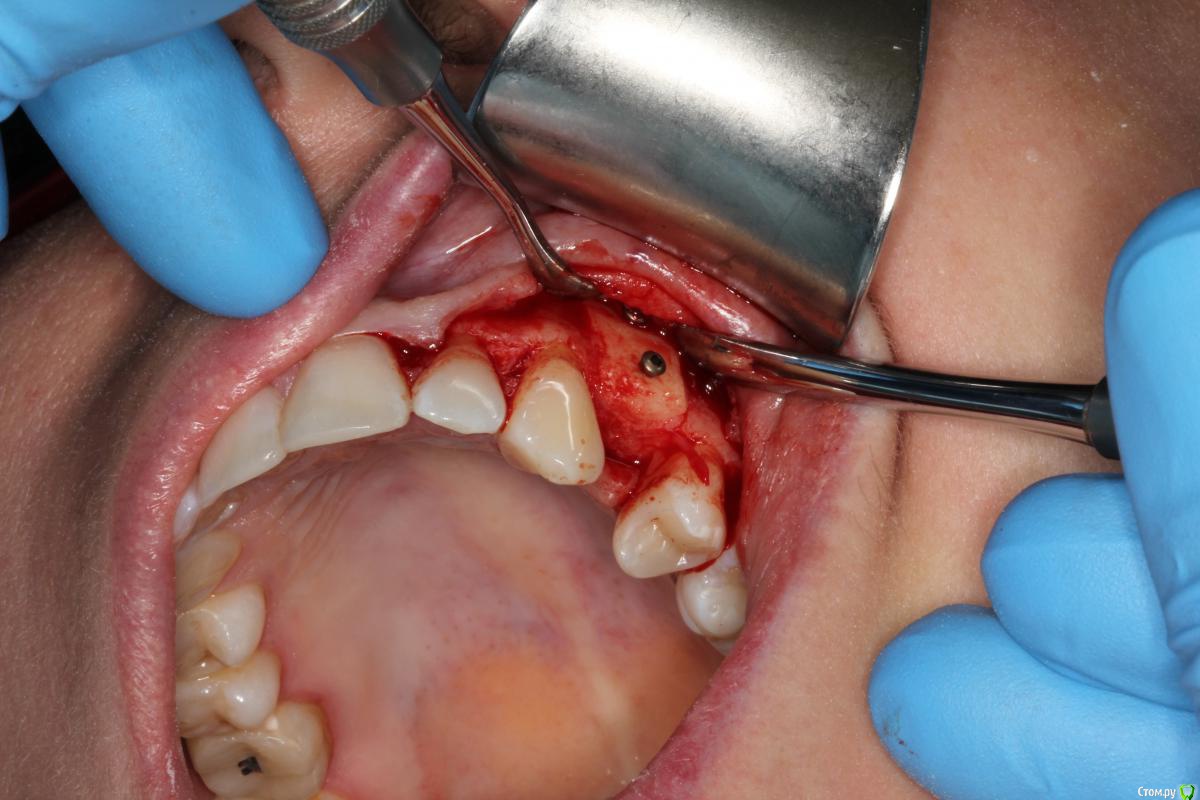

Den5 Опубликовано 24 декабря, 2014 Автор Поделиться Опубликовано 24 декабря, 2014 прикрутил аллоплант полгода назад.открылся.аллоплант норм-немного кровит.поставил Replace CC.Заглушил.Расщепил лоскут.Туда ССТ.На этапе ФДМ может еще подкину Ссылка на комментарий

Den5 Опубликовано 24 декабря, 2014 Автор Поделиться Опубликовано 24 декабря, 2014 фото снимков или рентген?Мембрана Evolution.Диастаз за штукатурен Putty Ссылка на комментарий

Den5 Опубликовано 24 декабря, 2014 Автор Поделиться Опубликовано 24 декабря, 2014 Усадка блока прогнозируема была?на 1-1,5 витка резьбы винта по-моему норм,на ауто было бы погрустнее Ссылка на комментарий

АнтонТЛТ Опубликовано 24 декабря, 2014 Поделиться Опубликовано 24 декабря, 2014 (изменено) Результат понравился Это блок с кортикалкой?Отслойка такая большая только для того чтоб винты выкрутить?Как пациенты относятся к алло? Изменено 24 декабря, 2014 пользователем АнтонТЛТ Ссылка на комментарий

Den5 Опубликовано 24 декабря, 2014 Автор Поделиться Опубликовано 24 декабря, 2014 Результат понравился Это блок с кортикалкой?Отслойка такая большая только для того чтоб винты выкрутить?Как пациенты относятся к алло?да,чтобы верхний винт выкрутить.блок с кортикалкой ,пациенту не говорил откуда блок,крепче спать будет 3 Ссылка на комментарий